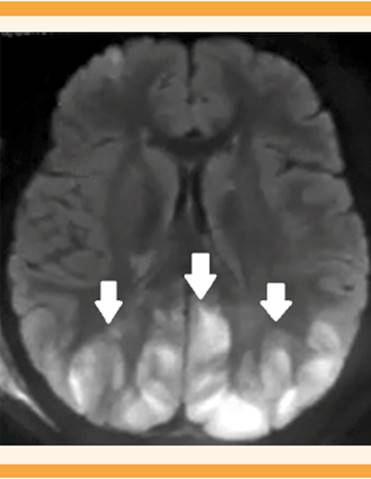

La resonancia magnética mostró imágenes hiperintensas en la región parietoccipital, simétricas, bilaterales en la sustancia blanca, sugerentes de síndrome de encefalopatía reversible posterior. Figuras 4y5

Figura 4 Resonancia magnética nuclear, corte transversal en fase FLAIR con imágenes hiperintensas en la región parietoccipital, simétricas, bilaterales en la sustancia blanca, sugerentes de síndrome de encefalopatía reversible posterior.

Figura 5 Resonancia magnética nuclear: corte sagital en fase FLAIR, con imágenes hiperintensas en la región parietoccipital, en la sustancia blanca, sugerente de síndrome de encefalopatía reversible posterior.